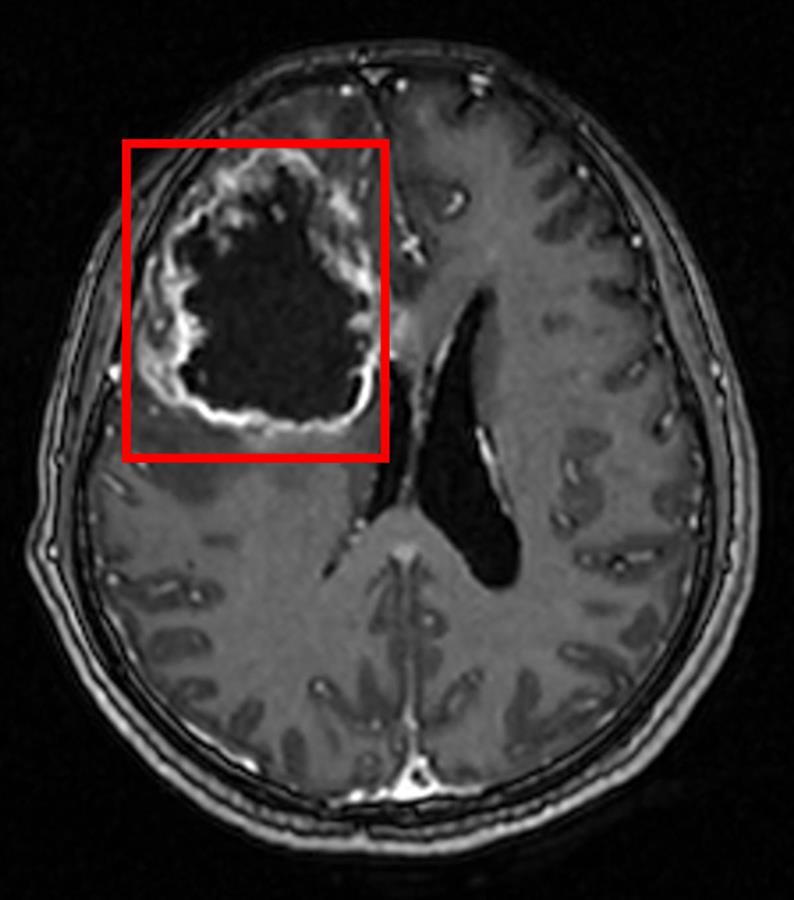

1个多月前,刘女士出现头晕、头痛、嗜睡症状,且精神非常差,10多天后这种症状明显加重,并伴有恶心、呕吐,去医院做头部磁共振检查发现,刘女士大脑右侧额叶巨大占位,医生怀疑是肿瘤性病变合并脑水肿。经过进一步检查后诊断,刘女士脑部的肿瘤符合胶质瘤的特点,肿瘤直径约6厘米。

直径6厘米的脑胶质瘤(通讯员供图)

刘女士的肿瘤恶性程度高,要尽可能地切除肿瘤,以保证生存期,同时,从生存质量来讲,也要尽可能地保留脑功能区,手术不仅棘手,难度也很大。